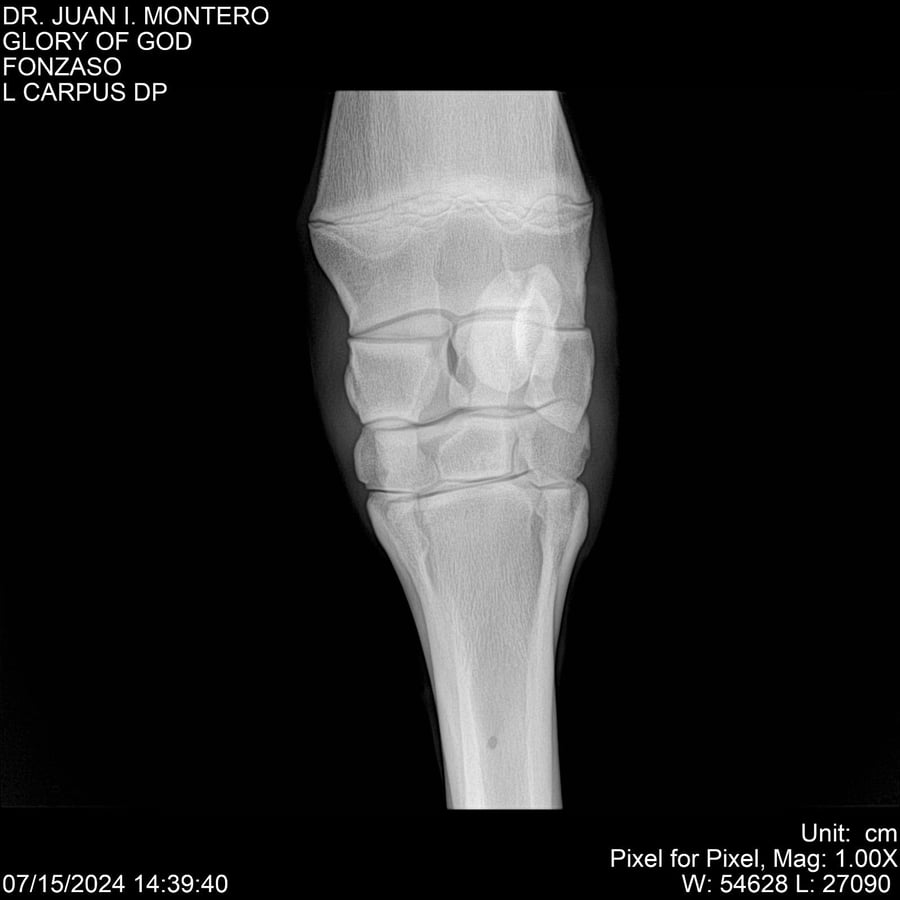

LOTE 10, GLORY OF GOD 🔥 🔥 🔥 Lote Anterior Volver al remate Lote Siguiente Ficha Contacto Montevideo - Ficha del Lote Identificador: #281389 Categoría: Yeguarizos Montevideo - 115 Visualizaciones ClicData Contacto Empresa: Abelenda N. R., Walter Hugo Nombre*: Teléfono* : E-mail* : Mensaje Enviar Registrese gratis Este contenido Exclusivo está disponible sólo para usuarios registrados Ingresar